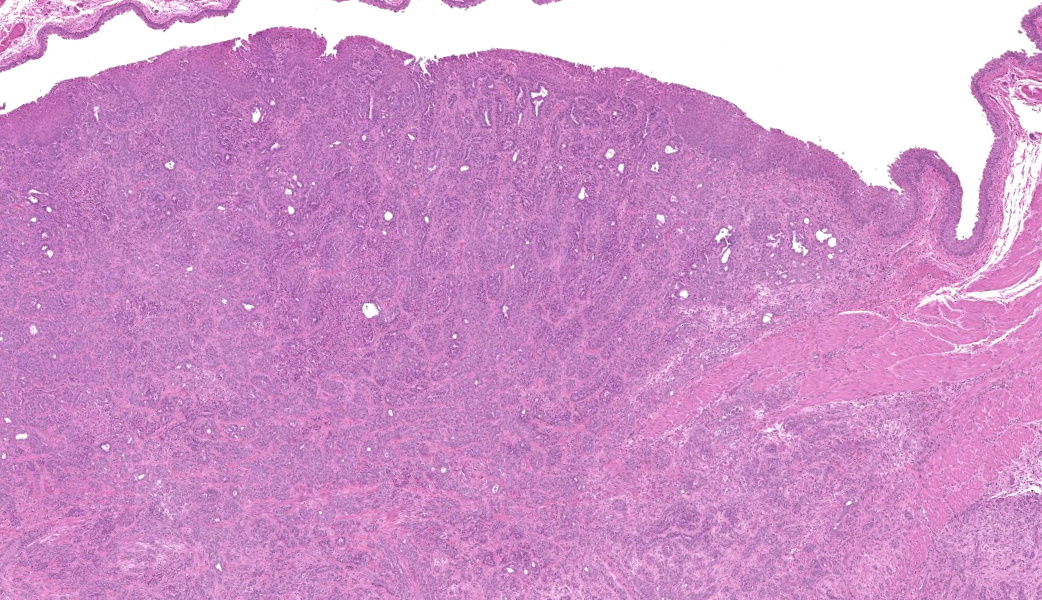

Urinary bladder: Arising from urothelium, infiltrating and expanding the lamina propria, and surrounding the ureter is a non-

encapsulated, well demarcated, moderately cellular neoplasm composed of polygonal cells arranged in nests on a fibrovascular stroma. Each neoplastic cell has indistinct cell borders, a moderate amount of pale basophilic cytoplasm, with a single misshapen nucleus with finely stippled chromatin and 1-3 distinct nucleoli. Anisocytosis and anisokaryosis are moderate. There are 2 mitotic figures per 2.37mm2. The neoplastic nests are often separated by a robust scirrhous response. Multifocally the neoplastic cells are replaced by eosinophilic, amorphous material (necrosis).

Urinary bladder: Urothelial cell carcinoma, Rattus norvegicus.

The cause of death in this animal is a ruptured urinary bladder secondary to outflow obstruction from a urinary tumor. The tumor observed both grossly and microscopically is consistent with a urothelial cell carcinoma of the urinary bladder epithelium. Spontaneous urothelial cell carcinomas of the urinary bladder are rare in rats. Although they may be locally invasive, they rarely metastasize. In this case, both the size of the tumor and the strong scirrhous response contributed to the outflow tract obstruction (and therefore an inability to urinate) and urinary inflow tract obstruction from the left kidney (resulting in unilateral hydronephrosis and hydroureter).

Differential diagnoses for this urinary bladder mass included urothelial cell carcinoma, prostatic carcinoma, and renal carcinoma, with the latter two included largely to ensure that metastatic or locally invasive disease was not being overlooked. The histologic architecture of an infiltrative epithelial neoplasm seemingly arising from the bladder wall favored a urothelial origin, but immunohistochemistry provided an additional layer of information. The neoplastic cells were diffusely immunoreactive for CK7, a cytokeratin expressed in most primary urinary bladder carcinomas.4 They were negative for GATA3, a transcription factor involved in urothelial differentiation, which may suggest prostatic carcinoma instead.5 However, Dr. Alves noted that GATA3 is most reliable in well-differentiated urothelial carcinomas, and its absence here is also consistent with less well-differentiated UCCs, as in this case.5 The tumor was also negative for PAX8, a marker of renal tubular epithelium, which helped exclude renal carcinoma.2 Uroplakin, a highly specific marker for urothelial cell carcinoma, unfortunately did not work in this case.7 Participants also discussed the glandular differentiation present within the tumor, which can be seen in both urothelial cell and prostatic carcinomas. In humans, glandular differentiation in urothelial carcinoma is associated with invasion and poorer differentiation.8 While extrapolating across species is something to be avoided, the same pattern was evident here.